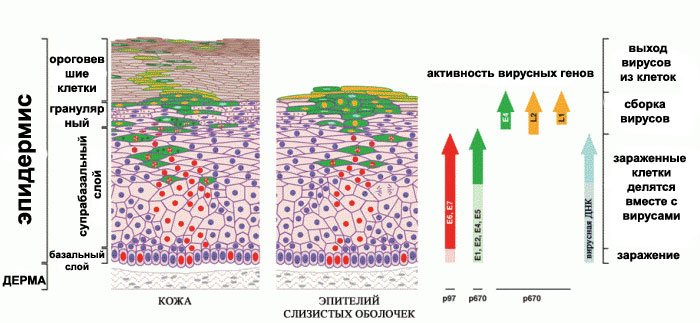

Факторы Риска ВПЧ: Визуальный Обзор и Информация

Раздел: Кладезь мудрости